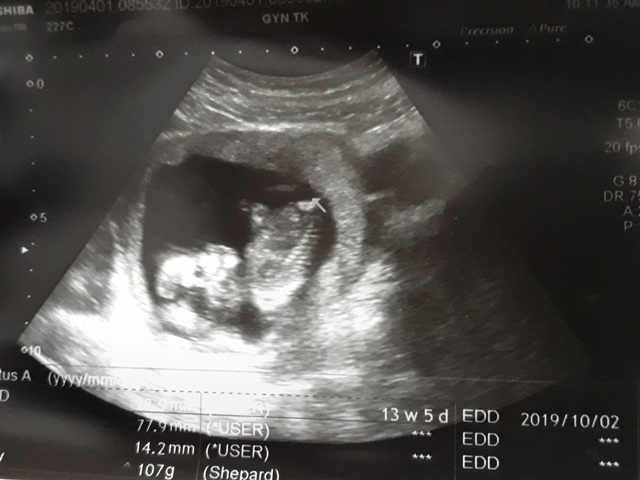

| 2019年04月01日 | 28.9mm | 77.9mm | 14.2mm | 107g | 153 |

| BPD:胎兒頭骨橫徑 AC:胎兒腹圍的長度 FL:胎兒大腿骨的長度 EFW:胎兒的體重 | |||||